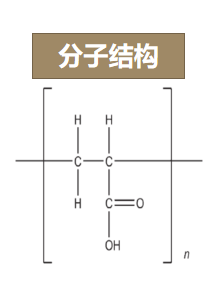

那卡波姆又是什么东西呢?

卡波姆(carbomer)又名卡波普、卡波普尔(carbopol)

成分有丙烯酸、烯丙基蔗糖交联的高分子聚合物

化学名为Carboxypolyanethylene

分子量在7×105~4×106左右